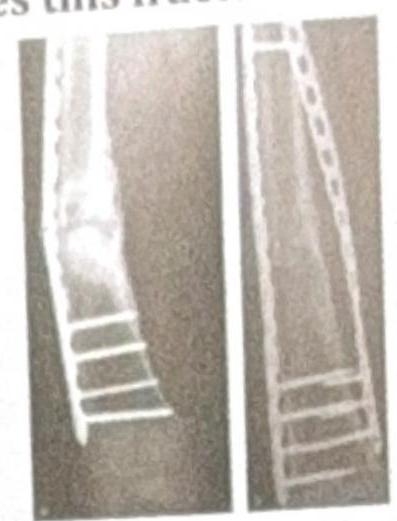

The X-ray shows plating done for a fracture. How does this fracture heal?

Explanation: **Primary healing** - **Plating of a fracture** aims to achieve **absolute stability** at the fracture site, which facilitates primary bone healing. - In primary healing, there is **direct bone formation** across the fracture gap without the formation of a significant callus. *Secondary healing* - Secondary healing involves the formation of a **callus** (fibrous tissue, cartilage, and immature bone) to bridge the fracture gap. - This type of healing occurs in situations with **relative stability** and some micromotion at the fracture site, such as with casting or intramedullary nailing. *Tertiary healing* - **Tertiary healing** is not a recognized term in the context of fracture healing. - Bone healing typically involves either primary or secondary mechanisms depending on the stability achieved. *Distraction histiogenesis* - **Distraction histiogenesis** is the process by which new bone is formed between bone surfaces that are gradually pulled apart using an external fixator (**distraction osteogenesis**). - This is used in procedures like **limb lengthening** and is distinct from the direct healing of a fracture fixed with a plate.